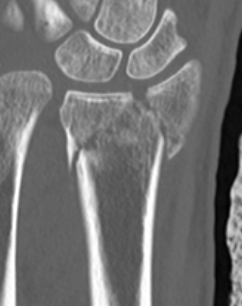

CT for further evaluation of articular congruency

Unacceptable reduction

1. Distal radial Step > 2mm

- leads to RC OA radiographically

- not proven to lead to dysfunction

2. Articular incongruency sigmoid notch / DRUJ > 2 mm

3. Radial shortening > 5 mm

- leads to ulnocarpal abutment

4. Radial inclination < 15o

5. Sagittal tilt

- > 15o dorsal

- > 20o volar

- +/- marked dorsal comminution